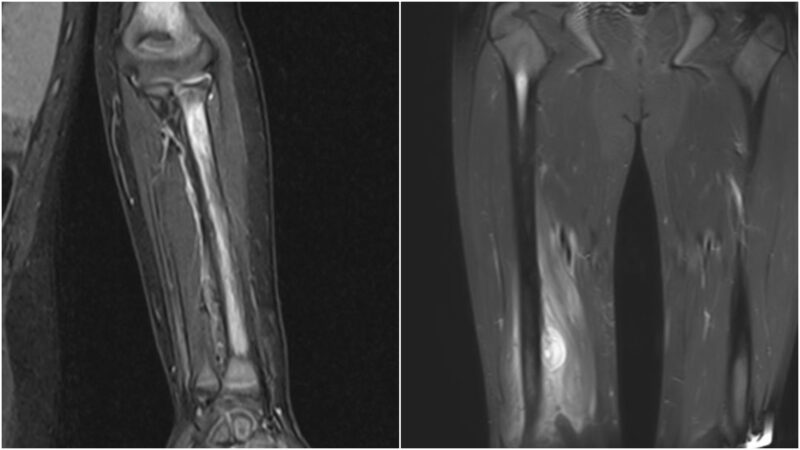

In SCD, the radiological findings in diseased bones, which include bone infarction and edema as a result of limited blood supply and recurrent VOCs, might trigger an inflammatory response locally and cause subperiosteal edema, which can be misinterpreted as infection (Figures 3 and 4). The breakdown of the cortex (Figure 5) by the pus indicates the acuity of the inflammatory process in the bone due to neutrophilic infiltration in response to bone marrow invasion by microorganisms, which indicates OM.

Figures 3 and 4: Bone edema and subperiosteal collection

Those radiological findings were grouped as less probable OM (probable), highly probable OM (definitive), and equivocal (suspected)9. The images were reviewed independently by two radiologists, and they agreed that the presence of cortical destruction was suggestive of OM, while the presence of bone edema, infarction, and subperiosteal edema was more in favor of VOC. The presence of the periosteal collection was equivocal and needed a clinical correlation for a definitive diagnosis of OM vs VOC.